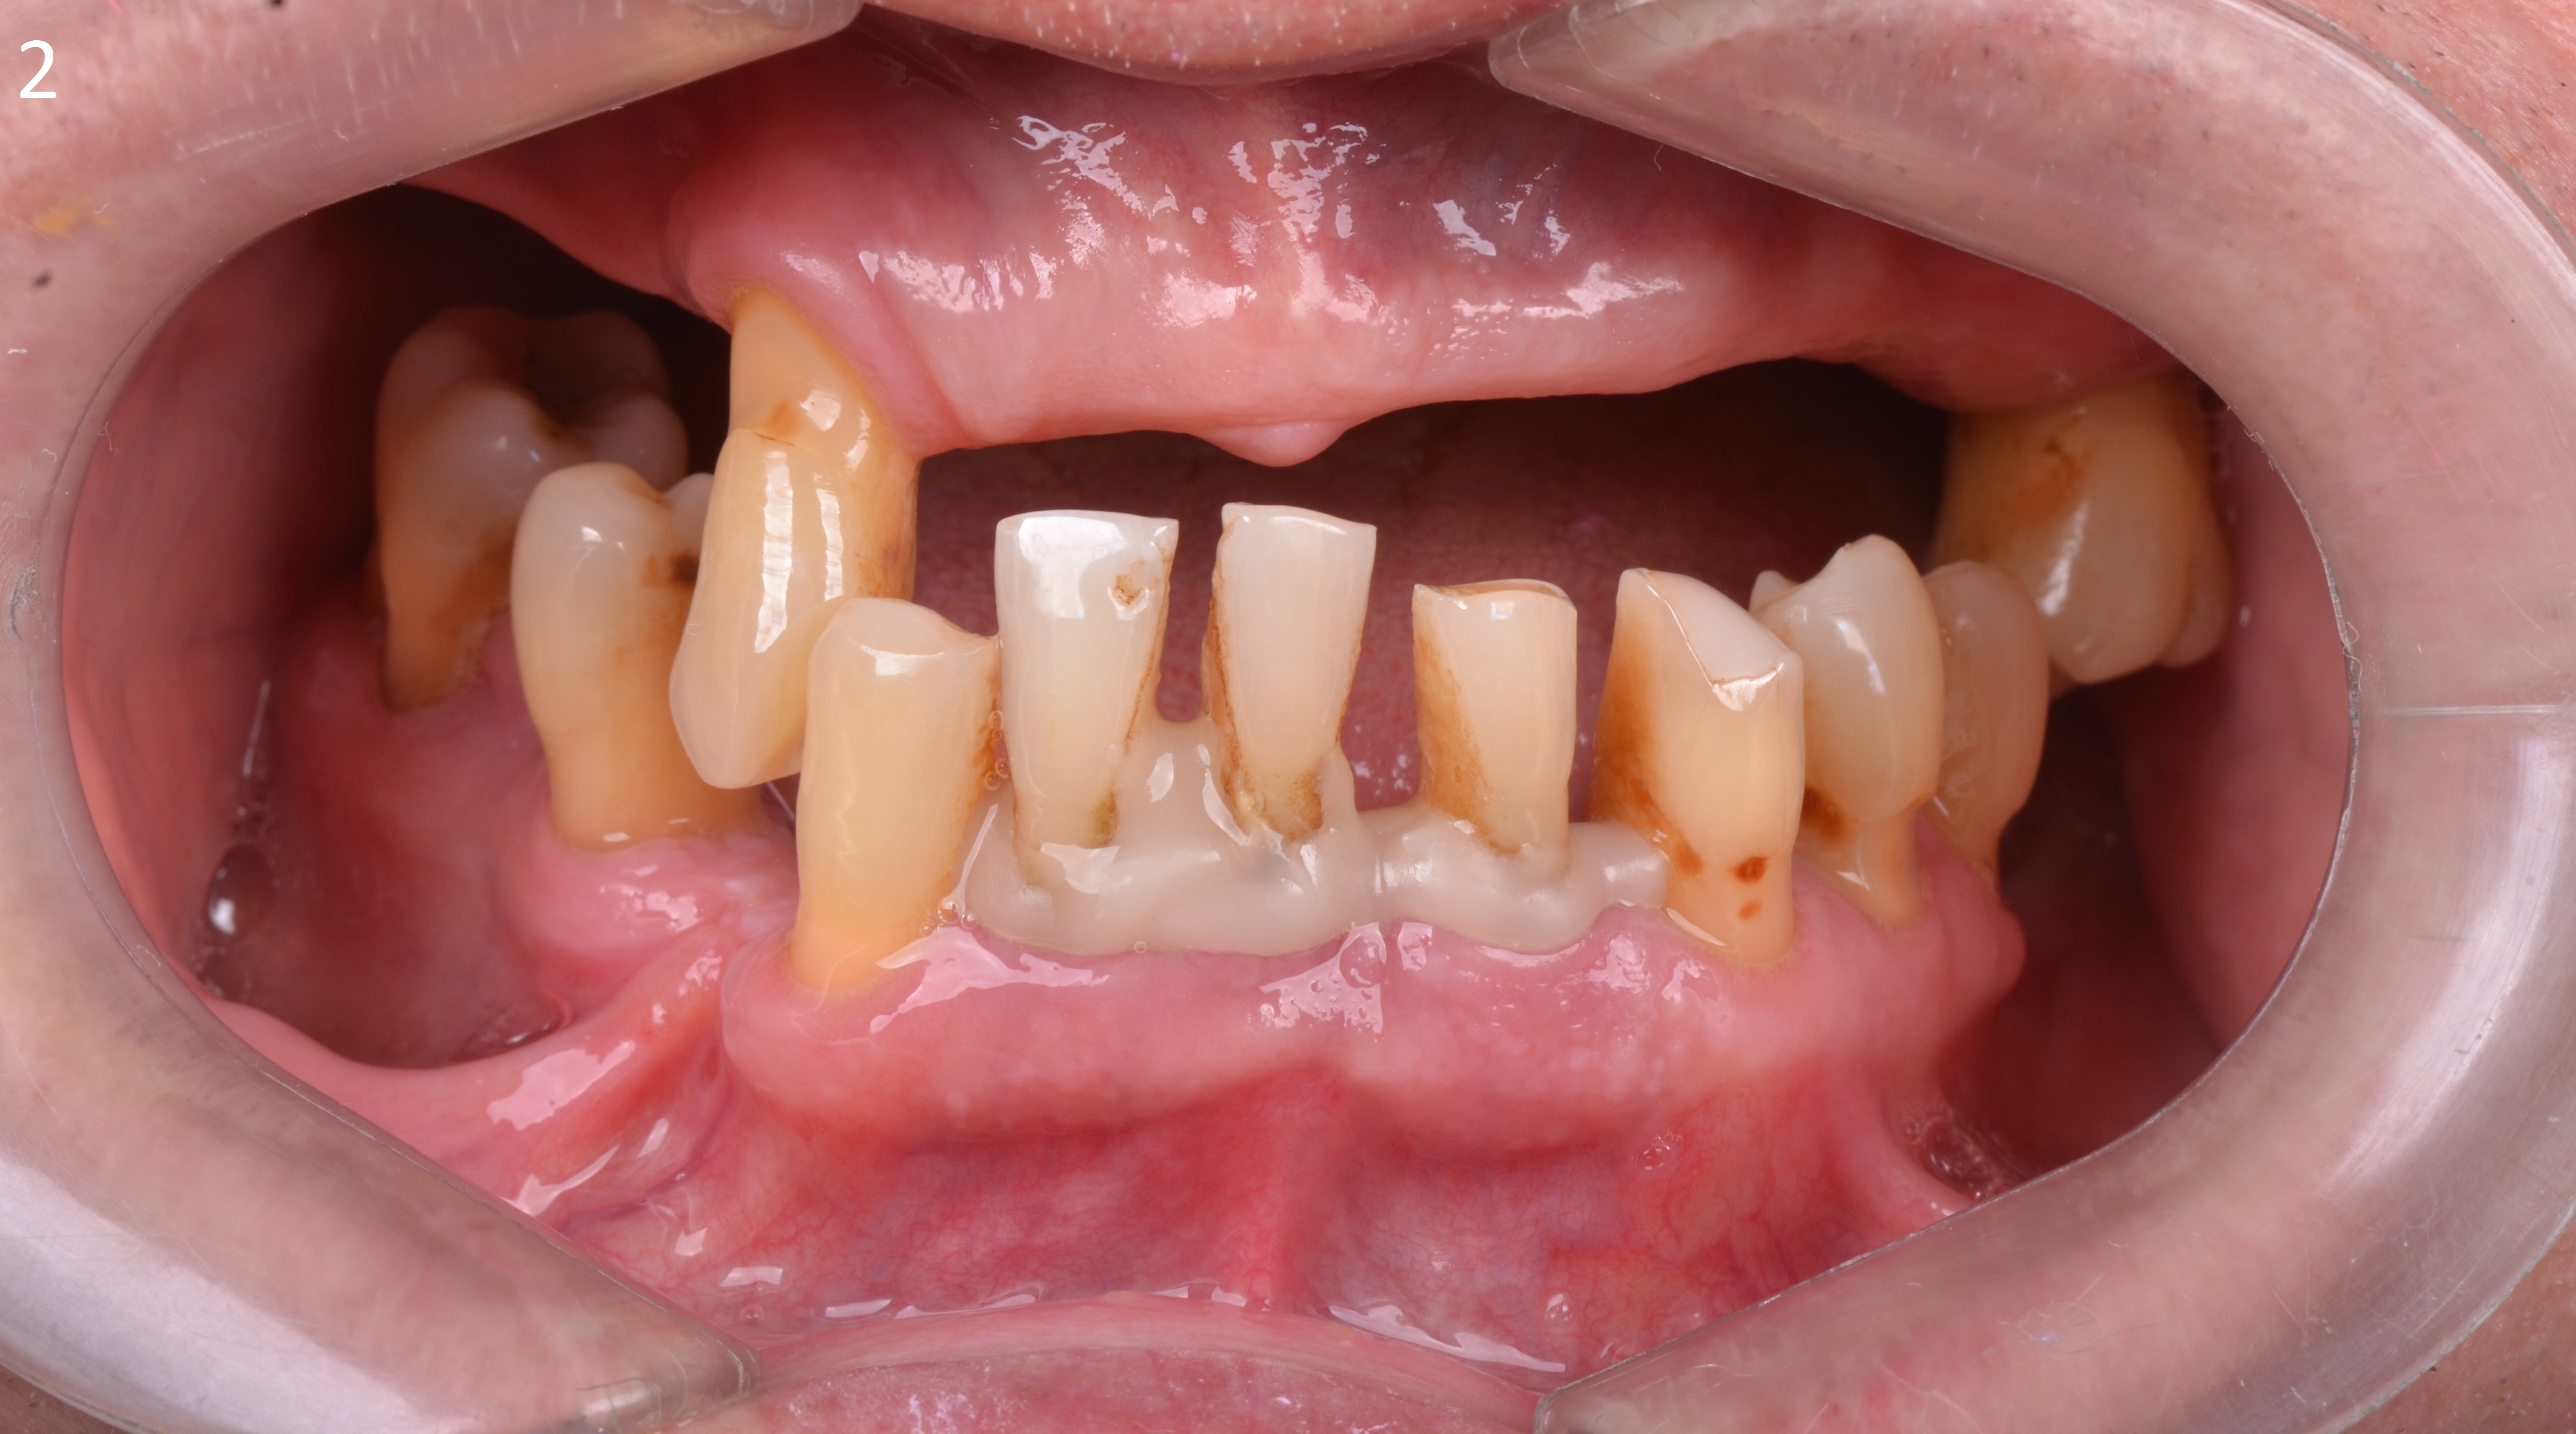

Пациент 65 лет обратился за комплексной стоматологической реабилитацией с жалобами на отсутствие зубов и эстетическую неудовлетворенность.

Пациент долгое время не обращался за стоматологической помощью, вследствие чего были утеряны зубы на верхней и нижней челюсти.

В полости рта наблюдаются пародонтальных патологии имеющихся зубов, зубоальвеолярное изменение в виде феномена Попова – Годона (рис 1,2,3.)